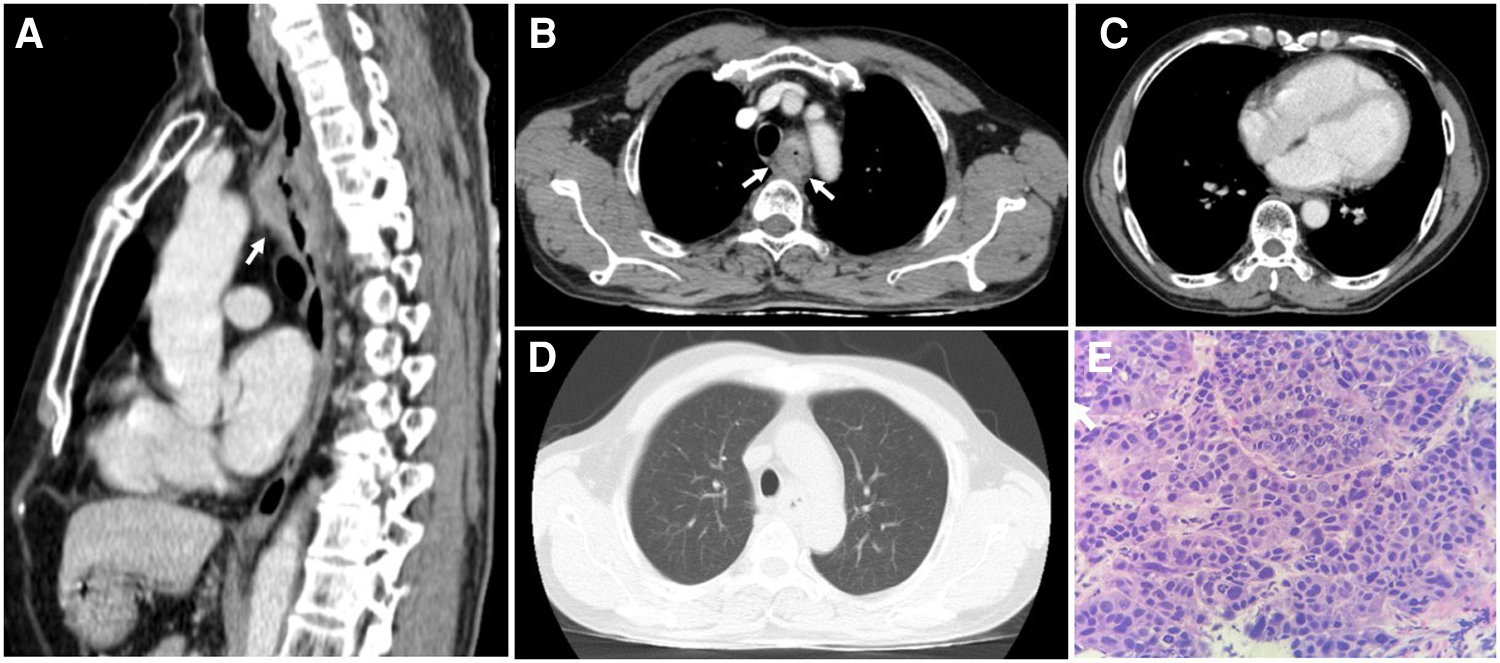

Figure 4

The thoracic computed tomography and histopathology before treatment strategy for esophageal squamous cell carcinoma. (A & B) The sagittal and axial planes demonstrate that the upper esophageal tumor does not invade the surrounding structures (white arrows). (C) The mediastinal window demonstrates normal thickness and density of ventricular and atrial walls. (D) No parenchymal lesions are seen on the lung window. (E) Hematoxylin and eosin-stained esophageal tissue at 400 × magnification showed tumor cells that possess enlarged, hyperchromasia, coarse nucleus; visible nucleoli and large cytoplasm. The tumor cells demonstrate disarray and loss of polarity in the desmoplastic stroma.

On thoracic MDCT, the mediastinal window showed infiltrative lesions causing abnormal wall thickening of the interventricular septum toward the apex, as well as of the inferior, posterior, and lateral walls of the left ventricle corresponding to the lesions observed on TTE. These lesions extended beyond the myocardium to the pericardial fat. The left anterior descending (LAD) artery and the left circumflex (LCx) artery were encased completely and compressed mildly. The adjacent pericardium was irregularly thickened (Figure 3F). These lesions were new in comparison with the pre-treatment film (Figure 4C). The ESCC was significantly diminished, and there was no longer abnormal esophageal wall thickening (Figures 4A, B; Figure 3E). On lung window, two new well-defined solid nodules in the left upper lobe and the right middle lobe were detected (Figures 3G, H) compared to before treatment (Figure 4D). On CMR, two tumors enhanced mildly on first pass perfusion images but had peripheral heterogeneous enhancement in post-contrast T1-weighted images with central necrosis. In addition, the tumors appeared to have restricted diffusion on the diffusion-weighted imaging (DWI) (Figure 3 A to D).